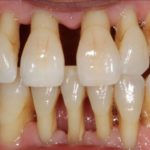

Стоматологи выделяют три степени протекания болезни. На первой и самой легкой стадии образуется карман в десне глубиной до 4 мм. Пока ощущения неприятные, но терпимые. Изменения в костной ткани еще не начались. Средняя степень тяжести характеризуется увеличением глубины кармана до 6 мм. Такой периодонтит симптомы имеет более явные: корни зубов слегка оголяются, десны воспалены, зубы становятся подвижными. Тяжелая стадия – это карман глубиной уже до 9 мм, сильное нагноение. Зубы меняют свое положение, а их подвижность настолько сильная, что не позволяет нормально питаться.

Верхушечный тип обычно не предполагает удаление зуба. Основная цель в данном случае – ликвидировать очаг воспаления, предотвратив заражение соседних зубов. Лечение каналов периодонтита сводится к удалению гноя или серозного образования в зубном канале, обработке антисептиком. В пораженный участок вводится турунда – марлевый тампон, смоченный лекарством. Канал закрывают временной пломбой, оставляют на 1-3 дня. После этого проверяют результат лечения, после чего назначают лекарства, мази, пасты при периодонтите для поддерживающей терапии, ускоряющие заживление.